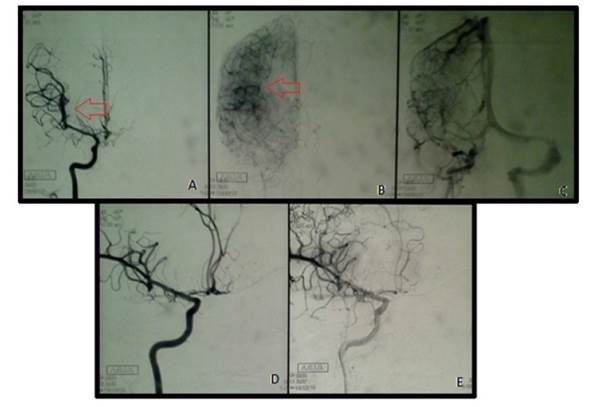

El estudio tomográfico demostró una lesión hemorrágica subaracnoidea tipo Fisher IV, con una colección hemática en el Valle Silviano derecho, territorio de la arteria cerebral media (Hunt y Hess II). Se solicitó una angiotomografía más embolización por diagnóstico de hemorragia subaracnoidea. Se le realizó una panangiografía cerebral con cateterización e inyección selectiva de las arterias carótidas internas y externas, y arteria vertebral izquierda que reveló un aneurisma sacular de cuello ancho de la arteria temporal anterior derecha de 2 x 2 mm con eje mayor hacia arriba y hacia afuera (figura 1).

Una vez realizado el diagnóstico de HSA por aneurisma (CIE-10: I60), localizado en la arteria temporal anterior derecha, se procedió al tratamiento endovascular con endoprótesis vascular y microespirales asociado a doble tratamiento antiplaquetario con aspirina, 100 mg/día y clopidogrel, 75 mg/día. Se utilizó una endoprótesis vascular tipo Lvis Jr de 3,5 mm x 23 mm (LVIS® Jr. Intraluminal Support 3,5 mm / 23 mm - MicroVention, Inc) previa antiagregación, además de microespirales (3D Detachable Coil 2 mm x 2 cm AxiumTM) entre las arterias cerebral media y temporal anterior derecha para obliterar el aneurisma y mantener permeable la circulación cerebral (figura 2). El procedimiento se realizó con la paciente bajo anestesia general con rocuronio 30 mg + fentanilo 200 μg + propofol 50 mg, y duró 2:30 horas. Durante el procedimiento la paciente no presentó ninguna complicación.